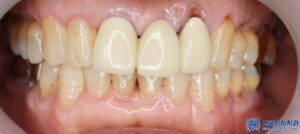

신경치료가 끝난 어금니는 치아를 보호하기 위해

크라운 치료를 진행하였습니다.

서울박사치과에서는 원내 기공소를 운영하고 있어,

더욱 정밀하고 빠른 보철 치료가 가능합니다.

이러한 장점 덕분에 환자분도

완성된 크라운의 색상과 모양, 착용감 등

모두 만족스럽다고 하셨습니다.

환자분은 전체적인 치료를 마친 후,

전체적으로 치아가 건강해진

느낌이 든다고 말씀하셨습니다.

특히 임플란트 수술 후 회복이 빠르고,

신경치료도 통증이 적었다는 점에서

큰 만족감을 보이셨습니다.